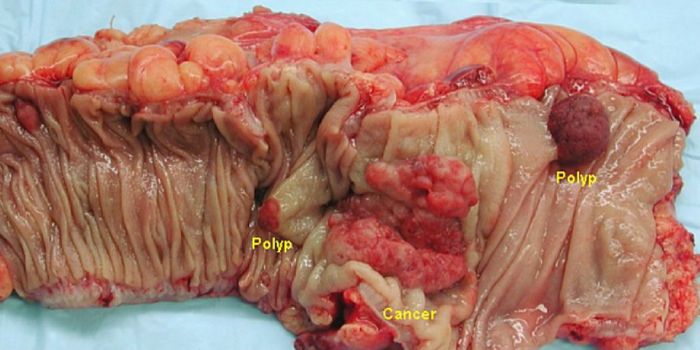

APR 13, 2017CancerThe onset of colon cancer may be tied to antibiotic use, reported scientists. The importance of the microbiome has only ...

JAN 31, 2017CancerThe importance of the microbiome has only being fully realized and appreciated in the recent years. And nowhere does the ...